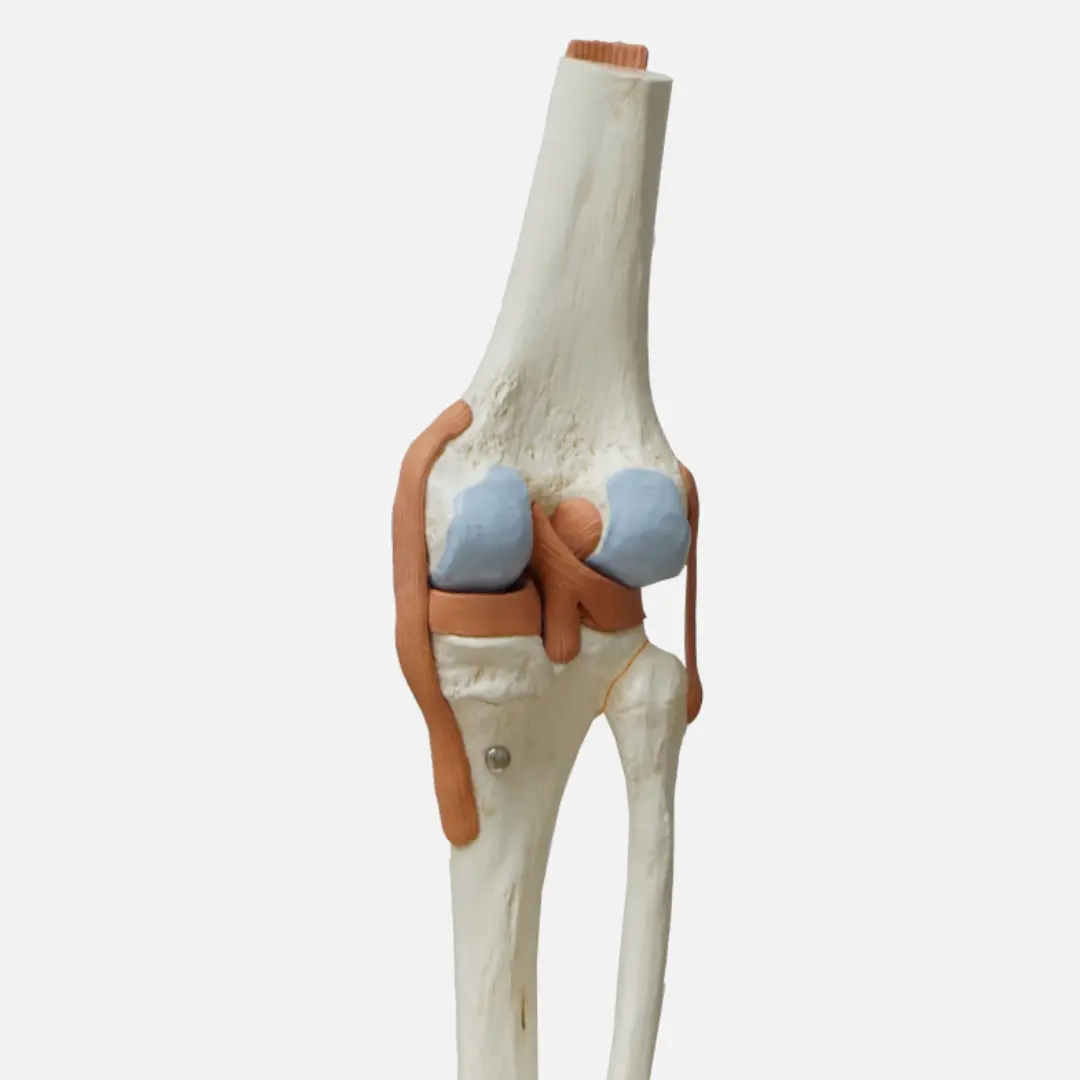

무릎 연골 손상의 치료 방법은 손상 정도와 환자의 상태에 따라 다양하게 결정됩니다. 초기에는 보존적인 치료를 우선적으로 시행할 수 있어요. 여기에는 약물 치료, 물리 치료, 주사 치료 등이 포함됩니다. 약물 치료는 통증과 염증을 완화하기 위해 소염진통제 등을 사용할 수 있습니다. 물리 치료는 근력 강화 운동, 스트레칭, 온찜질 등을 통해 무릎 주변 근육을 강화하고 관절의 움직임을 개선하는 데 도움을 줍니다.

주사 치료는 관절 내에 히알루론산이나 스테로이드 등을 주입하여 통증을 줄이고 관절의 윤활 기능을 회복시키는 방법입니다. 하지만 이러한 보존적인 치료에도 불구하고 증상이 호전되지 않거나, 손상 정도가 심한 경우에는 수술적 치료를 고려할 수 있습니다. 수술 방법에는 관절 내시경을 이용한 연골 봉합술, 절제술, 미세 천공술, 그리고 심한 경우 인공관절 치환술 등이 있습니다. 전문의와 충분히 상담하여 자신의 상태에 가장 적합한 치료 방법을 결정하는 것이 중요합니다.